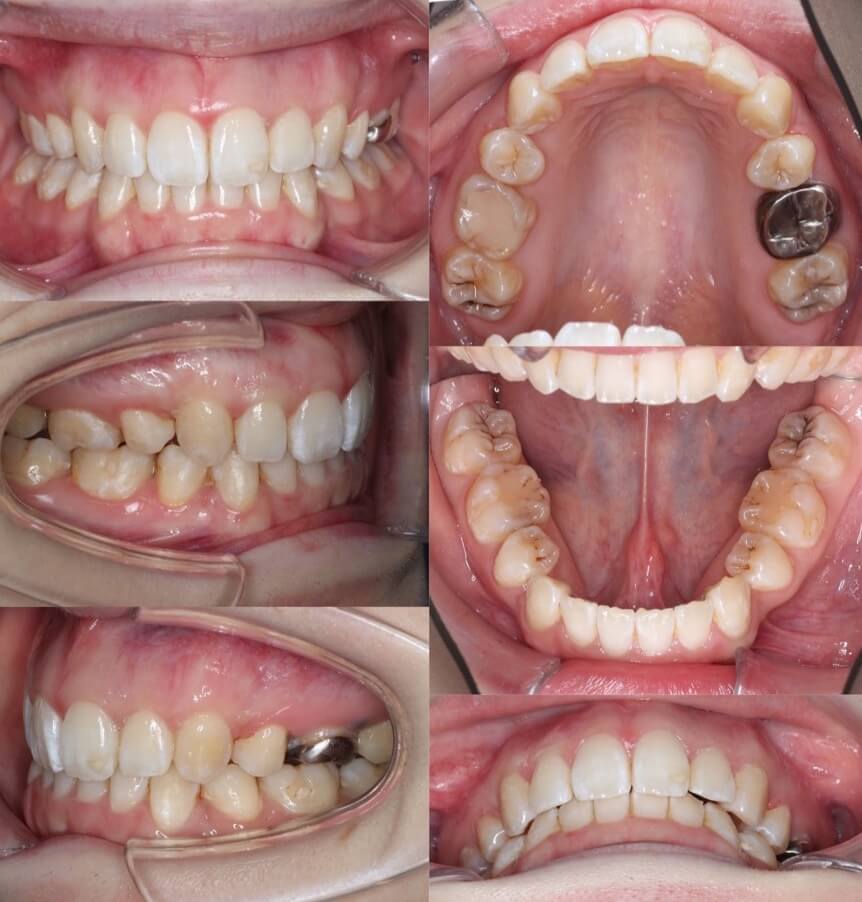

「あご先ができた」

大学生女性・唇側矯正・下あご後退型

<症例概要> 難易度:★★★☆☆

主訴:口元の突出

年齢・性別:大学生女性

住まい:千葉県八千代市

症状:下顎後退・上下顎前歯唇側傾斜

治療方針:抜歯空隙の閉鎖(最大固定)

治療装置:唇側矯正装置

固定:歯科矯正用アンカースクリュー(上顎頬側x2)

抜歯:上下第一小臼歯(計4本)

治療期間:2年2か月

リテーナー:上下プレートタイプ+フィックスタイプ

治療費用:968,000(税込)

代表的副作用:痛み・治療後の後戻り・歯根吸収・歯髄壊死・歯肉退縮

▶︎その他の副作用

アンカースクリューを使用して、最大限に上下の前歯を後ろに引っ張りました。前歯を後ろに引く量は事前にレントゲン分析による横顔のシミュレーションを行って決定します。このように最大限後方移動させる場合は、アンカースクリューなどの固定源の追加が必要になります。治療後は、あごのしわがなくなり、口元がかなり引き締まりました。